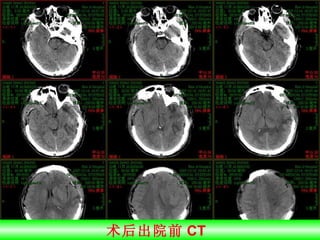

术后出院前 CT